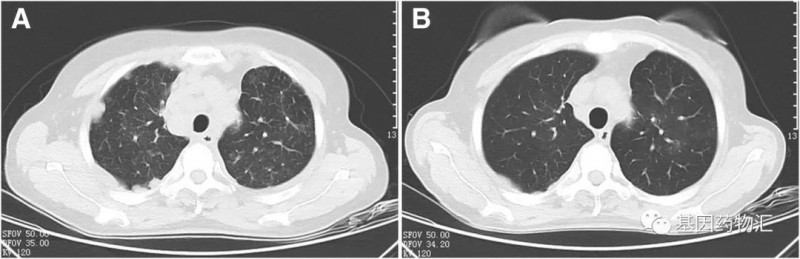

3个月后,胸部CT检查提示肿瘤体积增大,此时,基于胸水的二代测序(NGS)结果提示了新的ROS1-ADGRG6重排。

于是,患者开始接受口服克唑替尼治疗,仅1个月后,肿瘤大小就开始明显缩小,达到了临床部分缓解;至6个月后复查,疗效仍然保持稳定!